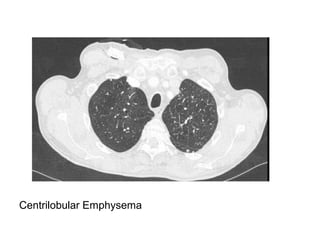

Centrilobular Emphysema